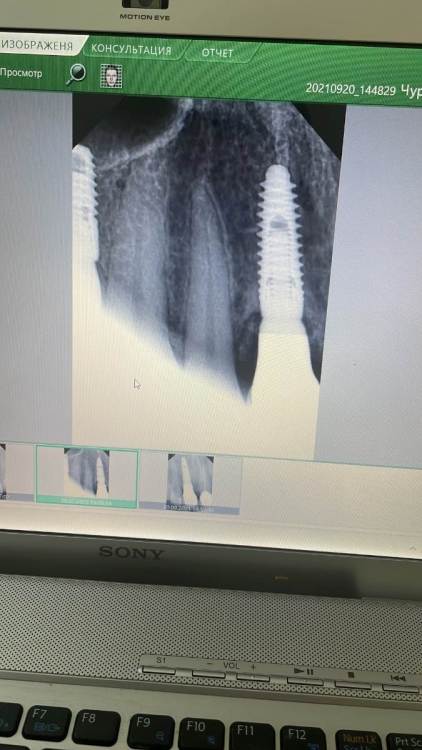

zubovolok Опубликовано 8 августа, 2023 Поделиться Опубликовано 8 августа, 2023 (изменено) Коллеги, приветствую. 2 года назад установил имплант (snucone) в позиции зуба 1.1, вестибулярно добавил био ос и резорбируемую мембрану, затем индивидуальный циркониевый абатмент на титановом основании и коронка на каркасе из диоксида циркония с нанесением. Три месяца назад пациент стал отмечать воспаление краевой десны м/у 1.2 и 1.1 - не кровит , ничего не выделяется, только внешне небольшой отек и гиперемия. Делали вектор - терапию 3 недели назад- не проходит . Метрогил- не помогает. Что это может быть ? Как исправить ситуацию? P.s - фиксация цементная. Снимки прилагаю- первый в день фиксации коронки в 2021 году , второй на сегодняшний день.Фото состояния десны нет. Изменено 8 августа, 2023 пользователем zubovolok Ссылка на комментарий

Aquarius Опубликовано 8 августа, 2023 Поделиться Опубликовано 8 августа, 2023 (изменено) Приветствую. -Контактный пункт ослаблен - Невидимый фрагмент цемента вестибуло-орально - Раскручен винт абатмента-микроподвижность-подтекание - Графт секвестрирует потихоньку Цифры глубины зондирования бы узнать Если прям совсем позанудствовать, то между 11,12 вроде цемент виден Изменено 8 августа, 2023 пользователем Aquarius Ссылка на комментарий